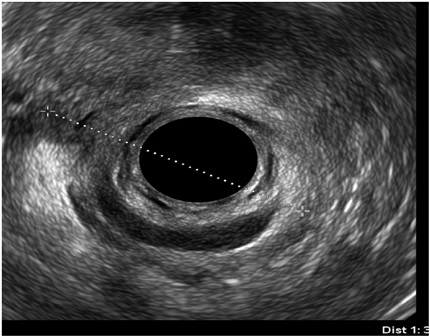

Diagnóstico endosonográfico final

Se encontró defecto de los esfínteres en 40 pacientes (29,41%), de los cuales 6 fueron hombres y 34 mujeres; aquí cabe anotar que el 93,33% (n =28) de las mujeres que tienen historia de incontinencia, también tienen antecedente de desgarro. De las 34 mujeres con defectos en los esfínteres, 32 lo tuvieron localizado en canal anal medio, con compromiso en nivel anterior, 1 de ellas con atrofia difusa de esfínteres, y otra con compromiso de canal anal inferior (figura 2).

Por otro lado, en el grupo masculino con estudio por incontinencia, el diagnóstico en todos fue cambios por atrofia del aparato esfinteriano, que pudo verse en cualquiera de las localizaciones del canal anal y que se evidenció como engrosamiento de los músculos en general y cambios difusos de la ecogenicidad de los mismos, sin posibilidad de determinar el borde que los delimita. Se encontró fístula perianal en 16 pacientes (11,8%); la principal forma de presentación de las fístulas fue transesfintérica (37,5%), seguida por las interesfintéricas y anovaginales (figuras 3 y 4). Doce pacientes presentaron absceso perianal (8,8%); de estos, el 83% correspondió a abscesos submucosos o isquiorrectales (figura 5).

Las medidas de los esfínteres están reportadas como normales en la gran mayoría de los casos, pero esto está influenciado porque dichas medidas se realizan a las “9” y “3” del reloj (aspecto lateral de los esfínteres), lo cual dista de la presencia de las alteraciones encontradas en las endosonografías por incontinencia, por ejemplo, que son en nivel anterior, y esta es la indicación más frecuente (24, 25, 26, 27).